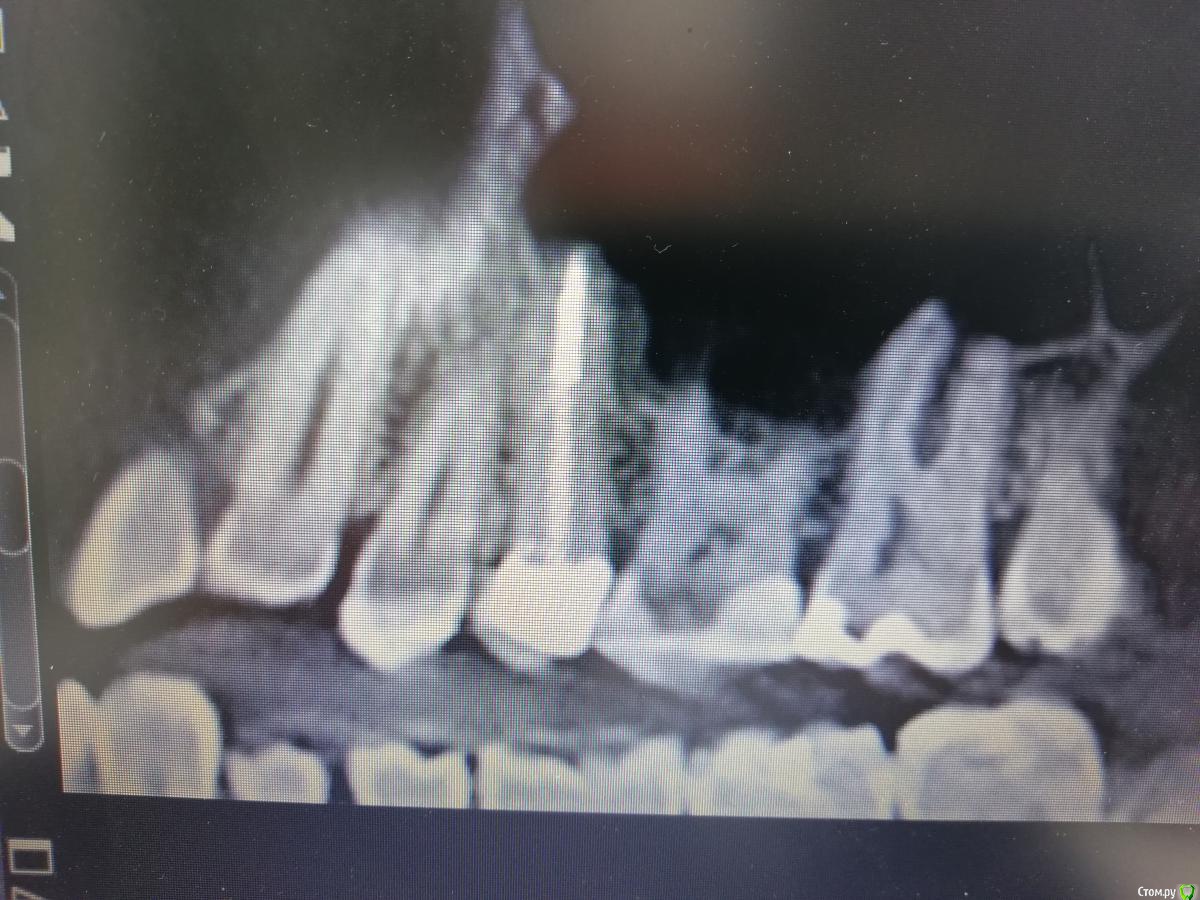

___49___ Опубликовано 22 марта, 2019 Поделиться Опубликовано 22 марта, 2019 (изменено) Адгезивная фиксация в канале - миф. Может она там и есть годик, но потом фигушки. Я вытащил не один десяток свш. за счет чего держится данный штифт (см.фото ниже)тогда по Вашему если , адгезивная фиксация там уже не работает , культя полностью из композита ? Снимок сделан в феврале этого года , а СВШ я ставил в 2011 году под емакс ( но пациентка в последствии изменила конструкцию) . И кстати мои СВШ поставленные ( именно так) обратно с расфиксацией или переломом не приходили . А вот такие работы с несколькими анкерами (ваше фото) , или как у ТС я бы переделал прежде чем одевать коронку . Кстати этот 15 зуб пролечил с "гранулемой" 4*4 мм после неудачного эндо кем-то в 2008 г . Изменено 22 марта, 2019 пользователем ___49___ Ссылка на комментарий

___49___ Опубликовано 30 марта, 2019 Поделиться Опубликовано 30 марта, 2019 Мы с Вами оба знаем , что в литературе описывается аргументированно погружение штифта от 1\2 до 3\4 при условии что над корневая часть будет меньше той что погружена в канал. Меня интересует обоснованность Вашего подхода - можете отправить по "адресу" где аргументированно описано почему "глубина засовывания" не имеет значения ... если то о чем Вы говорите имеет место быть я буду вынужден сопоставить оба подхода и взвесив плюсы и минусы выбрать какой из них лучше ... Ниже на рис. обозначен участок ослаблающий возможности зуба нести нагрузку который даже не компенсирован длинной штифта дабы распределить ее более равномерно - хотя судя по ширине канала тут можно было установить достаточно крупный штифт на хорошую глубину. но тем не менее даже при нарушении этих 2 условий несколько участников форума "лайкают" данный подход , хотелось бы услышать и их аргументированное мнение ЗА подобную установку штифтов. Может быть я чего-то не понимаю или не знаю или сопромат ошибается ( мысли вслух) . Ссылка на комментарий